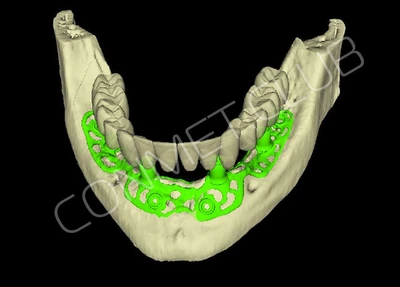

2. После этого произвели компьютерное моделирование самого имплантата и фиксирующих элементов. Примечательно, что в абатментах, использовался отлично зарекомендовавший себя и проверенный десятилетиями интерфейс КОНМЕТ! В результате получили несколько специальных файлов, позволяющих не только сделать сам имлантат, но еще до операции изготовить и сами зубы. Данные файлы передали в изготовление на специальном 3D оборудовании.

Имплантат напечатали из особого, биосовместимого, медицинского титана на предприятии имеющим соответствующую медицинскую лицензию. Толщина имплантата составила 0,8 мм, а вес всего несколько грамм!

Посмотрите на небольшом клиническом примере новый подход к конструированию имплантата по сравнению с имплантатами описанными в начале этой статьи.

Для просмотра проведите курсором мыши по изображению имплантата